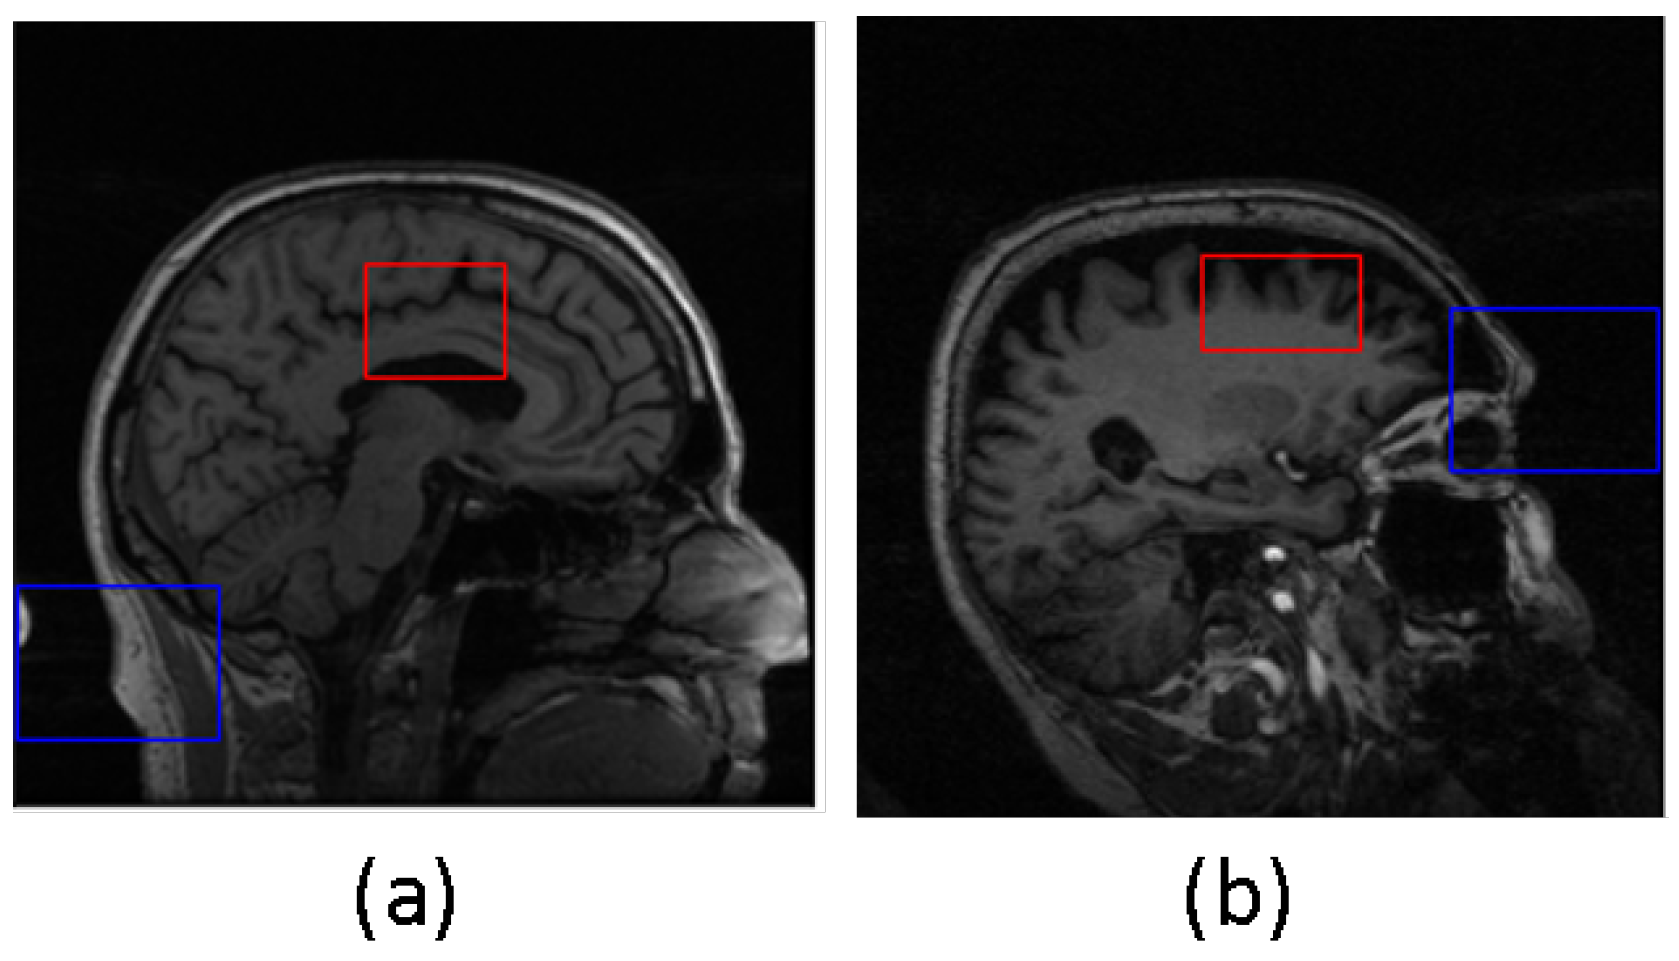

The samples in which the proposed algorithms perform poorly were not excluded from the final classification results. In Figure 5, two examples are presented where the predicted bounding box (shown in blue) accurately encompasses the ground truth hippocampal region (shown in red). In contrast, Figure 6 shows two instances where the agent fails to produce an acceptable bounding box. This issue can be attributed to two factors: firstly, as observed in the example shown in Figure 6a, the hippocampal region was correctly extracted but the agent failed to generate the bounding box that properly encloses the hippocampal region. Secondly, as seen in Figure 6b, the error lies in the accurate representation of the hippocampal ground truth itself.

Figure 6.

Poor localization outcomes from DQN. Blue box represents the predicted bounding box, and red box represents the truth hippacapus region. In (a) the hippocampal region was correctly extracted but the agent failed to generate the bounding box that properly encloses the hippocampal region. In (b) the error lies in the accurate representation of the hippocampal ground truth itself.